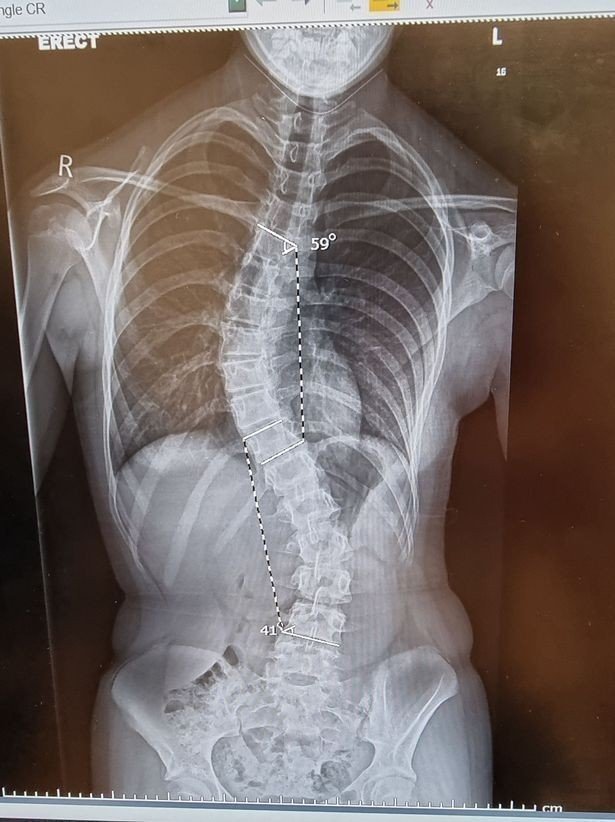

Yurt dışından birçok hastanın tedavi için Türkiye'yi tercih ettiğini belirten Ortopedi ve Travmatoloji Uzmanı Prof. Dr. Ahmet Alanay, "Özellikle son 7-8 yıldır İngiltere ve çevre ülkelerinden, Avrupa'dan hatta zaman zaman Avustralya, Yeni Zelanda, Güney Afrika gibi ülkelerden özellikle bu skolyoz tedavisi için bize gelen oldukça fazla sayıda hastamız var. Bu konuda dünyada öncü olduğumuz için en fazla tecrübeye sahip olan merkezlerden de biriyiz. Dünyanın birçok ülkesinde bu ameliyat hala daha yapılabilen bir ameliyat değil. Hastalar arasında çok ciddi bir bilgi ağı var. Hastalar birbirine yazarak burada aldıkları tedaviyi anlatarak zaman içinde oldukça fazla sayıda neredeyse bugün hastalarımızın yüzde 50'si buralardan gelen yabancı hastalardır diyebiliyorum. Bu tedavi için gelmeye başladılar. İngiltere'den sadece korse yaptırmak için buraya gelen hastalarımız olmaya başladı. Bunların bir kısmı ülkelerinde yapılamadığı için gelenler, bir kısmı bizim bu konuda artık ne kadar iyi olduğumuzu öğrendiği için. Özellikle skolyoz tedavisiyle ilgili bir tersine göç başlattık diyebilirim. Bu hasta bir genç kız, skolyoz deformitesi var. Korse ve egzersizlerle kontrol altına alınamamış, cerrahi tedavi gerekmiş. Şu anda onlarda mevcut olan yöntem hala daha klasik füzyon yöntemi fakat hasta dansçı olduğu için bu yöntem hareketi engellediğinden dolayı ve dans kariyerine de devam etmek istediği için bu VBT dediğimiz yöntemle ameliyat olmak istiyor. Bu yöntem Amerika'da, Almanya'da bizde yapılabilir. Hasta bunların üçünü de gezdikten sonra gerek tecrübe ve gerek etraftan duydukları, kendi doktorlarının tavsiyesiyle bizde ameliyat olmaya karar verdi. Kendisini zannediyorum Ağustos sonunda ameliyat edeceğiz" ifadelerini kullandı.

"Ameliyat sonrası hastanın dans kariyerine devam edebileceğini öngördüğünü ifade eden Alanay, "Tamamen esnekliğini koruyacak ameliyat için çok sınırda, bunu aileyle de konuştuk. Eğer iple, bantla gerdirme yöntemini uygulayabilirsek zaten onda hareket kısıtlılığı çok çok az, hemen hemen hiç olmadığı için full performans dansına devam edebilecektir. Hem sırtında hem belinde eğrilik var. Bence dans kariyerine kuşkusuz devam edecektir diye düşünüyorum" dedi.